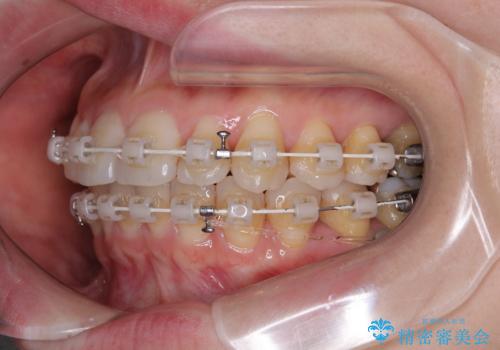

- 審美装置

- 1年3ヶ月

- 10-30回

デコボコ解消の際に、前歯が前突するリスクがあったため、舌突出癖の改善と、アンカースクリューによる加強固定を行うこととしました。

矯正治療後には奥歯の銀歯やむし歯をセラミックやゴールドにて治療を行い、大変整った口腔環境へと改善さ。れました